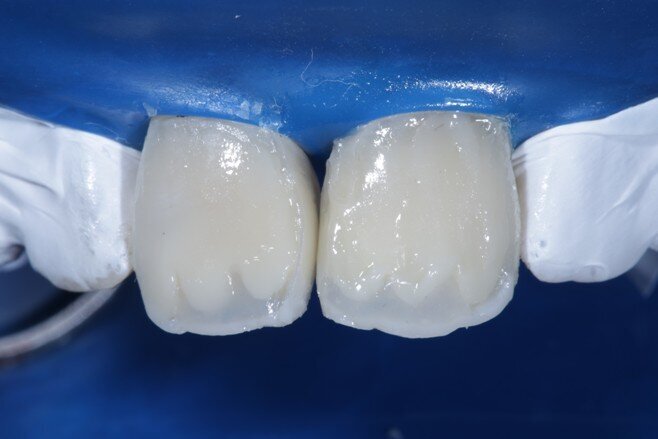

Two weeks later, the shade [ Fig 3 ] stabilized and the teeth were ready for bonding. We observed that the central incisors were still darker than the neighboring teeth. Direct composite veneers were planned with the help of a lab made wax up [ Fig 4 ] and a putty index. Bevels were placed and most of the preparation was in enamel. After the total etch protocol, 5th generation bonding agent was used. 3M Z350XT shades were used for the build up. A2 Enamel shade was used for the palatal shell [ Fig 6 ] and the proximal walls [ Fig 11 ].

Fig 6 Enamel shade for palatal shell on putty index

Fig 7 Enamel shade merged with the teeth